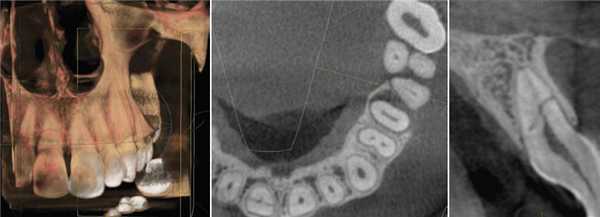

Лучевая диагностика добавочного нижнечелюстного канала

Врач-рентгенолог, руководитель медицинского отдела по ЮФО рентгенодиагностических центров «Пикассо», ассистент кафедры лучевой диагностики КубГМУ, руководитель учебного центра «Пикассо» ЮФО.

Раздвоенный канал нижней челюсти

Журнал: Стоматология. 2018;97(1): 63‑66

Описаны варианты раздвоения канала нижней челюсти (НЧ), которые были выявлены как случайные находки при конусно-лучевой компьютерной томографии челюстно-лицевой области пациентов, обращавшихся в медицинские центры за стоматологической помощью. Выявленные добавочные каналы в теле НЧ начинались от верхней стенки нижнечелюстного канала и имели небольшую протяженность. Они заканчивались в ретромолярной области, направлялись к корням зубов или ориентировались параллельно основному каналу НЧ.

Удвоение канала нижней челюсти — НЧ (нижнечелюстного канала) — вариант его анатомического строения. О нем имеется упоминание в национальном руководстве по хирургической стоматологии и челюстно-лицевой хирургии [1], а также в ряде научных статей, авторы которых обнаружили дополнительный канал (ы) на анатомических препаратах [2, 3]. Частота выявления нескольких каналов НЧ при анализе ортопантомограмм (ОПМГ) — 0,08—0,95% [4]. Конусно-лучевая компьютерная томография (КЛКТ) выявляет наличие раздвоенного канала в 15,6—64,6% случаев [5—7]. В соответствии с классификацией M. Naitoh и соавт. [5] различают 4 типа канала (рис. 1). Рис. 1. Конфигурация раздвоенного канала НЧ (по M. Naitoh и соавт. [5]). 1-й тип: передний канал — дополнительный канал сливается с основным (а) или оба они идут параллельно (б); 2-й: щечно-язычный канал — расположен со щечной (в) или язычной (г) стороны от основного канала; 3-й: дентальный канал — ведет к корням зубов (д); 4-й: ретромолярный канал — заканчивается ретромолярным отверстием в одноименной ямке (е).

Цель исследования — описать варианты топографии каналов НЧ, выявляемые с помощью КЛКТ.

Необычные варианты хода канала НЧ были выявлены как случайные находки при исследовании на КЛКТ челюстно-лицевой области пациентов, которые обращались в медицинские центры Минска в период 2015—2017 гг. за стоматологической помощью. Авторы исследования не ставили перед собой задачу определить частоту встречаемости удвоения канала НЧ в популяции.

Рентгенологическое исследование проводилось на аппарате Galileos GAX5 («Sirona Dental Systems, Bensheim», Germany). Анализ полученных данных проводился по традиционной методике, предусматривающей последовательное изучение сначала срезов в 3 взаимно перпендикулярных проекциях (окно мультипланарной реконструкции), затем срезов, расположенных продольно и поперечно относительно зубной дуги (в окне «Панорама»), а также томограмм произвольной кросс-секции, оптимальной для получения изображений анатомических объектов соответственно их пространственному положению. Оптимальными для визуализации вариантов ветвления канала НЧ являлись реформаты вдоль продольной оси ее тела, которые обозначаются по терминологии разработчиков аппарата как «касательные».

Результаты и обсуждение

Ниже представлены описания рентгенологической картины раздвоенного канала НЧ 3 типов.

Пациентка Е., 48 лет. С левой стороны на уровне угла НЧ от нижнечелюстного канала отходила боковая ветвь (рис. 2). Рис. 2. Ретромолярный канал; КЛКТ пациентки Е., 48 лет. 1 — канал НЧ; 2 — ретромолярный канал; 3 — подбородочное отверстие. Ее поперечный диаметр составлял 1,37 мм у места начала и 0,96 мм в области ретромолярного отверстия.

Поперечный диаметр канала НЧ у места начала ветви — 3,08 мм. Сначала дополнительный канал направлялся вперед. На расстоянии 5,33 мм от места бифуркации он образовывал петлю, менял направления хода и шел назад и вверх, заканчиваясь отверстием в ретромолярной области. Описанный ход характерен для ретромолярного канала (4-й тип раздвоенного канала НЧ). На контралатеральной стороне дополнительных каналов НЧ не обнаружено.

Пациентка Ф., 55 лет. С правой стороны на уровне угла челюсти от верхней стенки нижнечелюстного канала начинался дополнительный канал с поперечным диаметром 1,52 мм (рис. 3, а). Рис. 3. Дентальный канал нижней челюсти. а — КЛКТ пациентки Ф., 55 лет; б — КЛКТ пациентки К., 29 лет. 1 — канал НЧ; 2 — дентальный канал; 3 — подбородочное отверстие. Поперечный диаметр основного канала на этом же уровне — 2,70 мм. Дополнительный канал направлялся полого вперед и вниз параллельно основному каналу НЧ. В мезиальном направлении кортикализация стенок дополнительного канала постепенно уменьшалась, и достоверно проследить его ход удалось до уровня зуба 4.7. Описанная картина характерна для дентального канала (3-й тип раздвоенного канала НЧ). С левой стороны визуализация дополнительного канала была недостоверной: выявлялось линейное просветление такой же локализации и направления, как с правой стороны, но картины трубчатого образования не выявлено, вероятнее всего — вследствие недостаточной кортикализации его стенок.

У пациентки К., 29 лет, с левой стороны обнаружен дентальный канал (см. рис. 3, б). В месте отхождения он имел вертикальный диаметр 1,35 мм (приблизительно в 3 раза меньше вертикального диаметра канала НЧ на этом же уровне), направлялся вперед и вниз, располагаясь параллельно основному нижнечелюстному каналу, и на уровне медиального корня зуба 3.7 круто поднимался вверх. Дентальный канал переставал идентифицироваться на уровне средней трети корня второго нижнего левого моляра. С правой стороны раздвоения канала НЧ не выявлено.

Пациентка Б., 57 лет. С правой стороны на уровне угла НЧ определялась добавочная ветвь нижнечелюстного канала диаметром 1,1 мм, которая, начинаясь от его верхнего контура, далее шла вперед почти параллельно основному каналу на протяжении 8,01 мм, а затем сливалась с ним (рис. 5). Рис. 5. Конфигурация канала НЧ; КЛКТ пациентки Б., 57 лет. 1 — канал НЧ; 2 — передний канал. На контралатеральной стороне добавочных каналов не обнаружено. Описанная рентгенологическая картина соответствует 1-му (а) типу раздвоенного канала НЧ.

По данным литературы, чаще всего встречаются 4-й и 1-й типы раздвоенного канала Н.Ч. Среди прочих вариантов анатомического строения канала они были обнаружены соответственно в 52,5—71,3 и 18,8—44,3% случаев [4—7]. Щечно-язычный и дентальный тип канала выявлялись в 0,5—8,3% наблюдений. В общей популяции, по данным L. Haas и соавт. [8], на ОПМГ и КЛКТ-сканах частота встречаемости ретромолярного канала составляет 4,20%, а всех других типов раздвоенного канала — 16,25%.

У человека нижний альвеолярный нерв обычно имеет 3 ветви, которые формируют нижнее зубное сплетение [9]. 1-я (ретромолярная) ветвь параллельна основному стволу и иннервирует третий моляр. 2-я (молярная) ветвь отходит от основного ствола или ретромолярной ветви, идет параллельно n. alveolaris inferior и отдает зубные ветви. 3-я (резцовая) ветвь является продолжением главного ствола нерва в мезиальном направлении. У плодов человека, по данным M. Chávez-Lomeli и соавт. [10], каждая из указанных ветвей располагается в отдельном костном канале. Авторы предположили, что образование раздвоенного канала связано с неполным слиянием этих каналов.

Выявление особенностей хода канала НЧ на этапе планирования стоматологических манипуляций имеет важное практическое значение. При удалении третьего моляра, зубной имплантации, эндодонтическом лечении, а также при плоскостной остеотомии ветви НЧ, из-за повреждения сосудисто-нервного пучка в дополнительном канале НЧ могут развиваться ятрогенные осложнения — неожиданное профузное кровотечение во время операции, парестезия, анестезия и формирование травматической невриномы в послеоперационном периоде [6, 11].

Присутствие ретромолярного канала предполагает наличие дополнительного источника иннервации третьего моляра, который может служить причиной неблагоприятного исхода мандибулярной анестезии [12].

Обнаружение в НЧ добавочных каналов представляет собой несложную задачу при наличии высокотехнологичных методов рентгенологической визуализации, таких как КЛКТ, и владении врачами-стоматологами соответствующими знаниями и практическими навыками.

Канал НЧ при типичной локализации визуализируется в виде трубчатого костного образования, стенки которого представлены тонкими линейными затемнениями кортикальных пластинок, а содержимое канала отображается в виде интенсивного просветления. Калибр канала постепенно уменьшается в мезиальном направлении. Достоверным признаком наличия дополнительного канала является продолжение в его стенку кортикальной пластинки основного канала. Это дает возможность проследить дополнительный канал на всем его протяжении. У места его начала канал НЧ, как правило, имеет локальное расширение. Дополнительные каналы обычно отходят от верхней стенки канала НЧ и имеют небольшую протяженность.

Анатомические варианты локализации каналов в теле НЧ многообразны. Тем не менее обнаружение основного и добавочного канала в месте предстоящих манипуляций предопределяет эффективность дентальной имплантации и других хирургических операцией на НЧ.